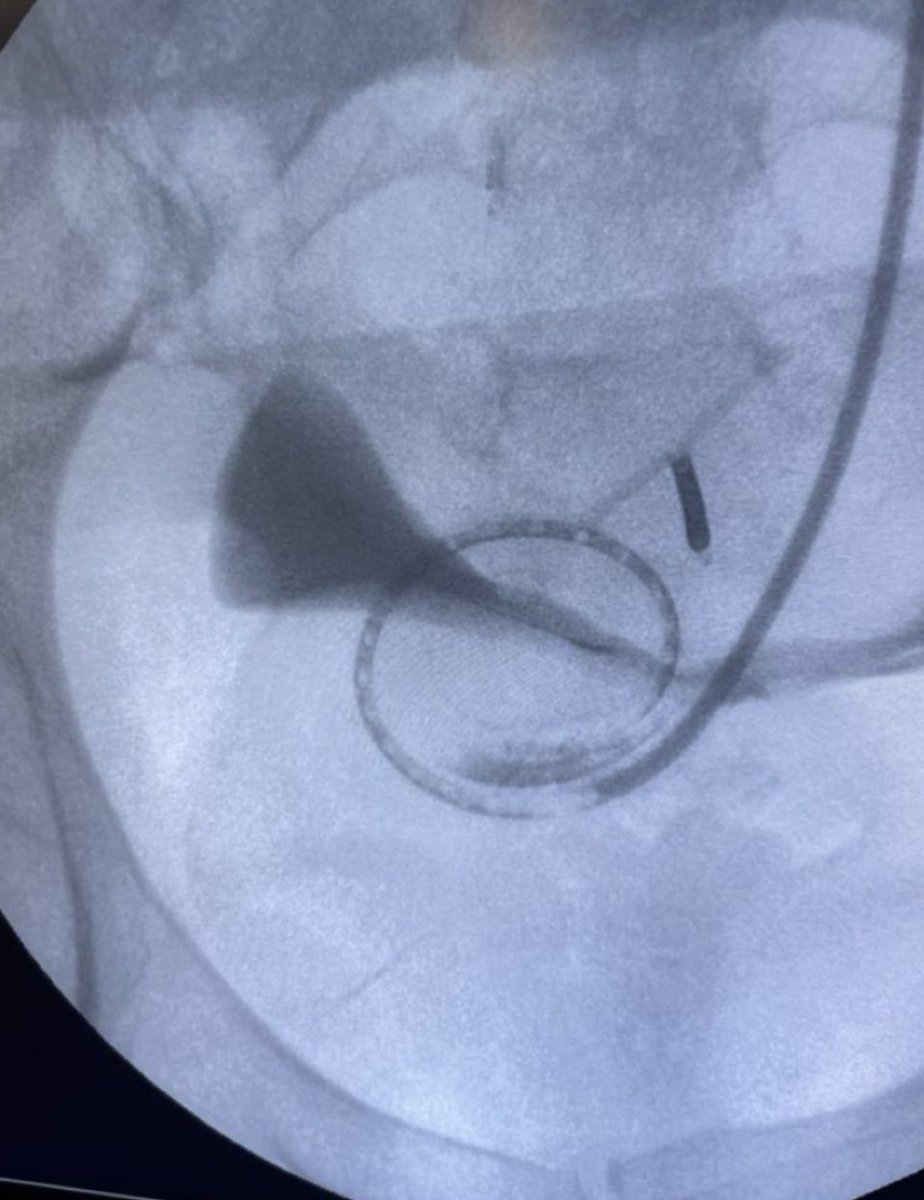

@IntervenNephMx Making history with collaborations from 15 hospitals and more than 20 interventionalists in one project... @ISNWCN @isn